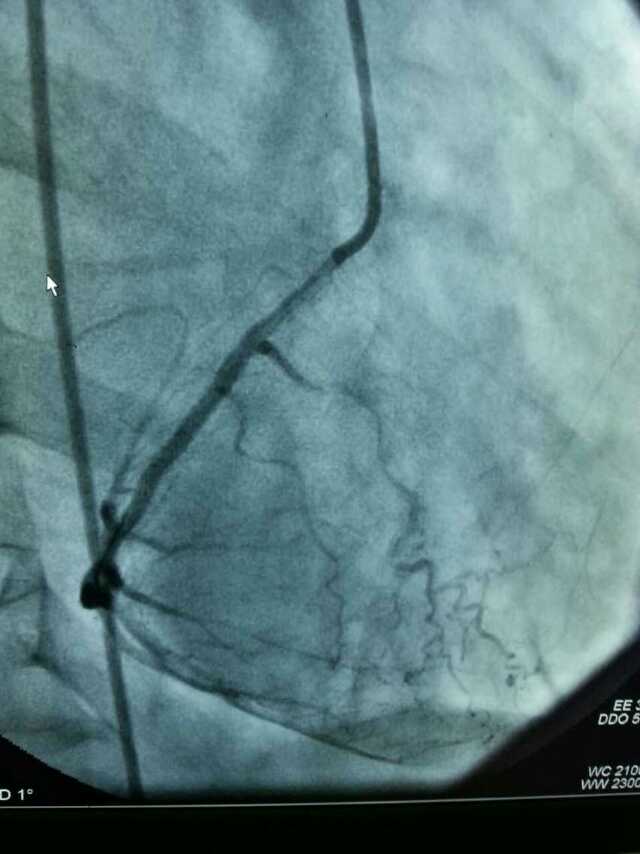

3月20日,家住翔安的庄先生为感谢跳蛋视频 心血管内科的医护人员在第一时间对他的病情给予明确诊断,并及时采取有效治疗措施,让他的心脏病很快得到康复回家。特地送来一面写着“德医双馨,妙手回春”锦旗以表达他们满满的感激之情。